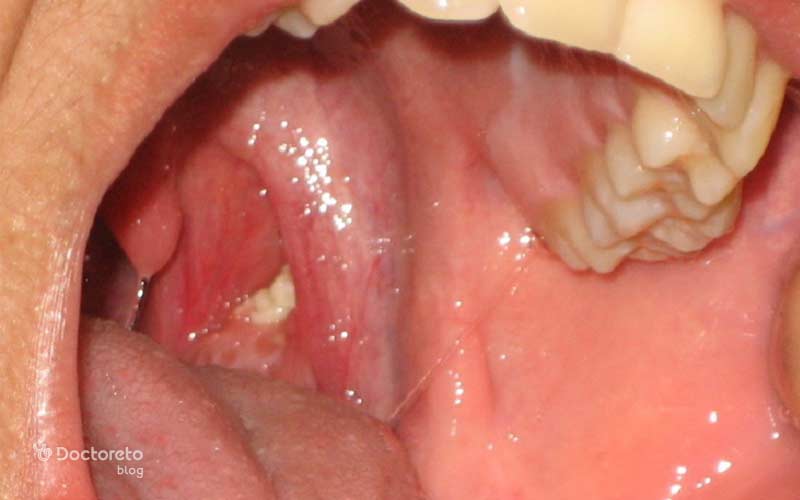

عکس لوزه حفره دار و سنگ دار

سنگ لوزه تودههای کوچک و سفتی هستند که در حفرهها یا کریپتهای لوزه تشکیل میشوند. این سنگها از تجمع مواد معدنی مانند کلسیم، بقایای غذا و میکروارگانیسمهایی مانند باکتری یا قارچ به وجود میآیند. اگرچه معمولاً خطرناک نیستند، اما گاهی اوقات باعث بوی بد دهان و احساس ناراحتی در گلو میشوند.

کریپتهای لوزه بهطور طبیعی به سیستم ایمنی کمک میکنند تا عوامل بیماریزا را شناسایی کند. با این حال، زمانی که این حفرهها بزرگ یا ملتهب شوند، احتمال تجمع مواد و بروز علائمی مانند گلو درد، گوشدرد یا التهاب مزمن افزایش مییابد.